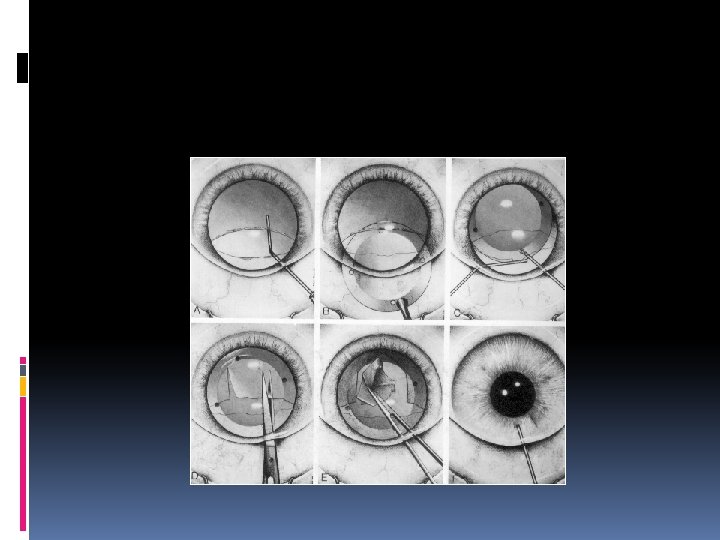

CAN-OPENER CAPSULOTOMY DEFINITION - A ragged but circular opening in anterior capsule made by creating multiple punctures

TECHNIQUE 2 mm perforation into anterior chamber at limbus AC is formed with VE Cystotome or double bent 26 G needle used Punctures in anterior capsule made from 6 o’clock position parallel to dilated pupil margin

TECHNIQUE contd. . Proceed in clock wise direction in circular fashion Removal of circular capsular flap with Kelman Mac Pherson forceps